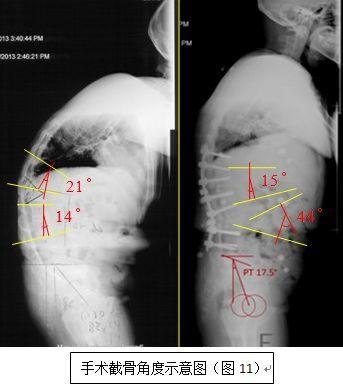

强直性脊柱炎后凸畸形

男14岁,先天性脊柱侧后凸

先天性脊柱侧弯畸形 l3椎体半椎体畸形 腰椎侧后突畸形